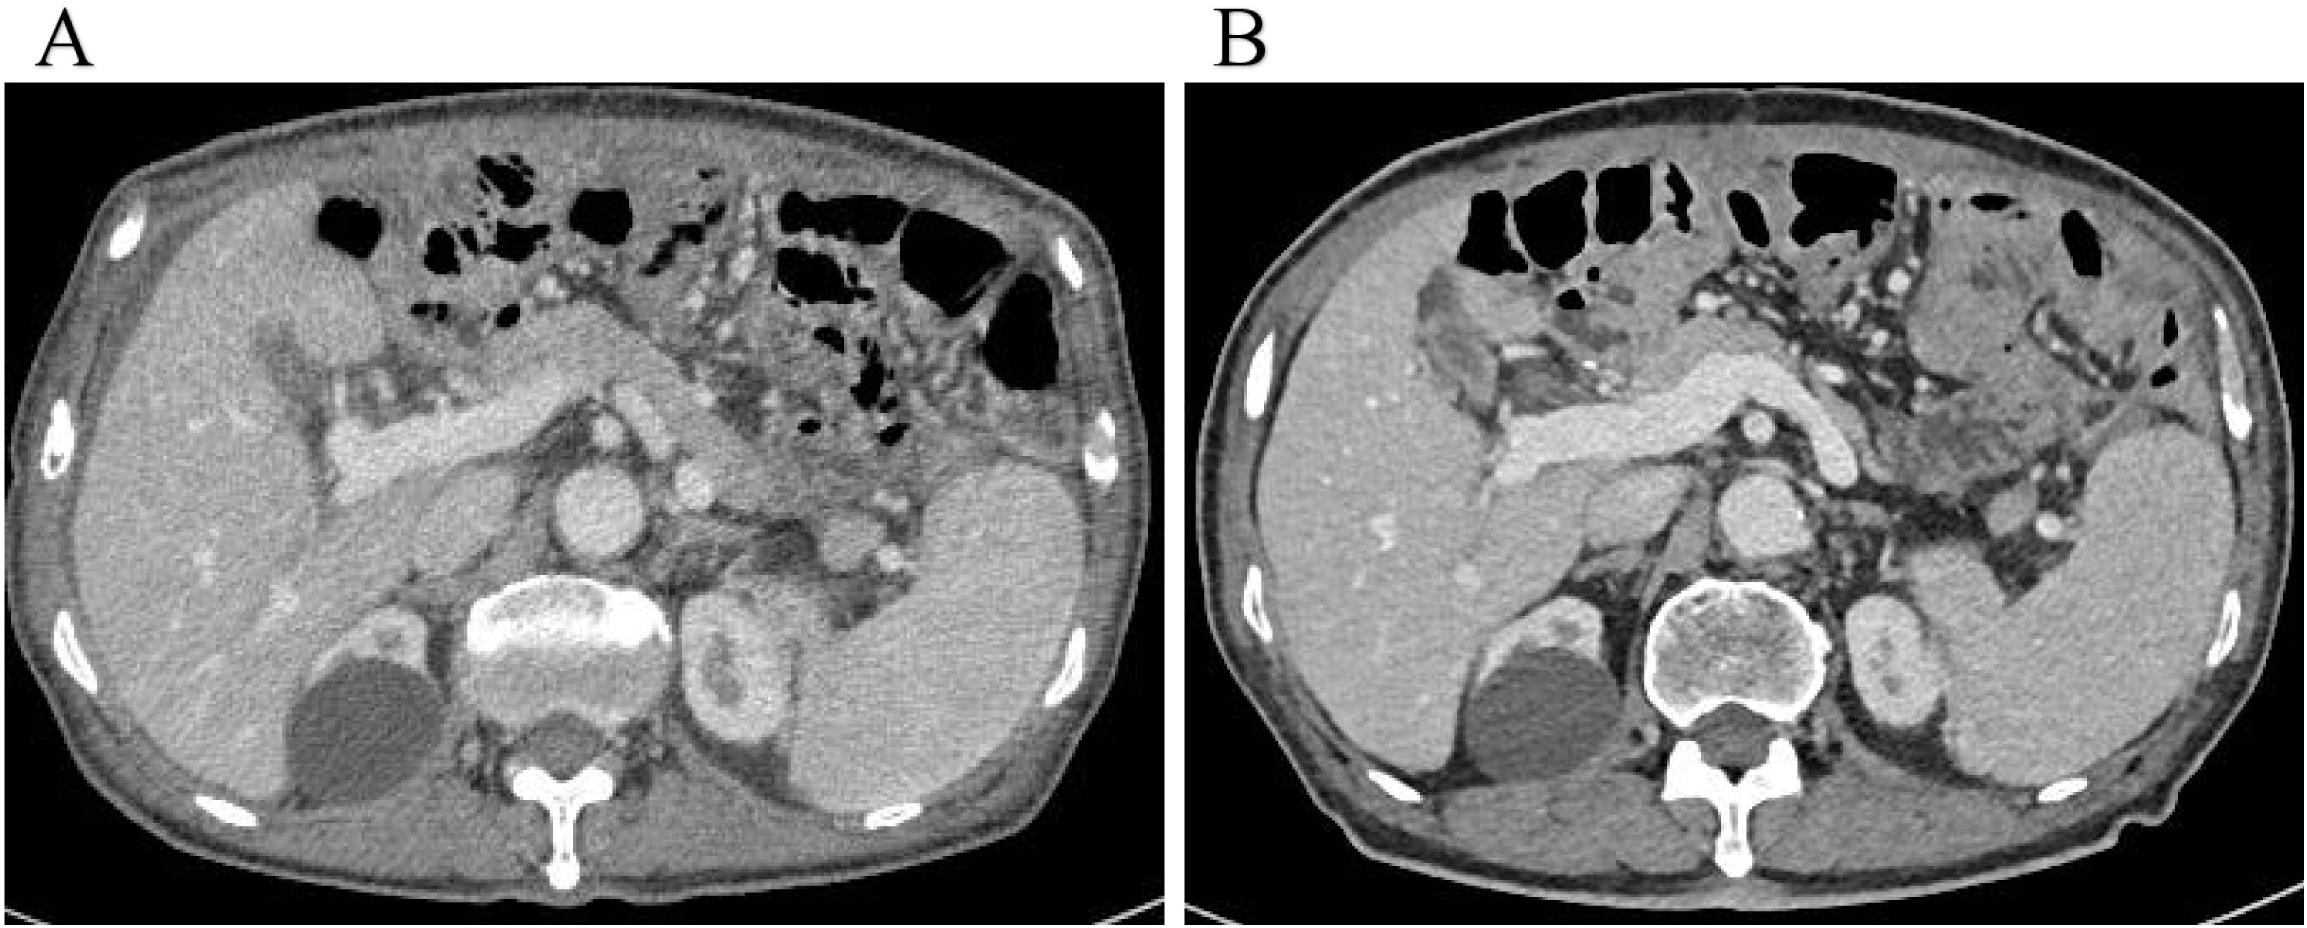

Figure 2

(A) PET-CT imaging demonstrated no findings suggestive of tumor recurrence; (B) Enhanced abdominal CT revealed a significant accumulation of fluid in the abdominal cavity compared to previous findings (August 2023).

Five days after the final HIPEC session, abdominal ultrasound revealed no residual ascites, and the perfusion catheters were removed before discharge. The patient was very satisfied with the treatment effect and would continue with systemic palliative chemotherapy in the oncology department subsequently. Surveillance abdominal CT scans performed in May and October 2024 showed no recurrence of ascites (Figure 4).

Figure 4

(A, B) Surveillance abdominal CT scans performed in May and October 2024 showed no recurrence of ascites.